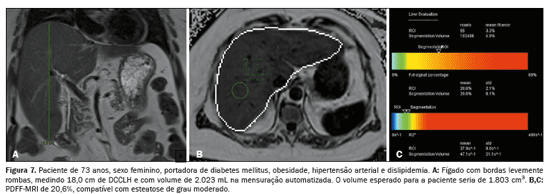

A associação, tanto do DCCLH e a PDFF-MRI (rs = 0,474;

p < 0,001) quanto da Voe e a PDFF-MRI (rs = 0,568;

p < 0,001), apresentou correlação estatisticamente significante, refletindo os resultados das análises anteriores (Figura 5). A relação entre o acúmulo de gordura e o aumento do volume hepático está exemplificada nas Figuras 6, 7 e 8.